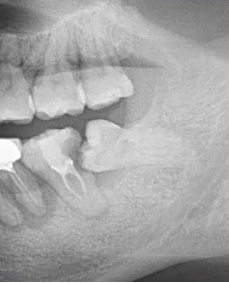

【病例1】

9岁,男孩,因右上面颊部肿胀来源就诊

55深龋→根尖炎→面颊肿胀

曲面断层片怎么看口腔精读 | 一次性教你看懂曲面断层片!_https://www.jmylbn.com_新闻资讯_第27张

根尖片视野范围较小,曲断检查结果:乳5颌骨根方有含牙囊肿的存在。

曲面断层片怎么看口腔精读 | 一次性教你看懂曲面断层片!_https://www.jmylbn.com_新闻资讯_第28张